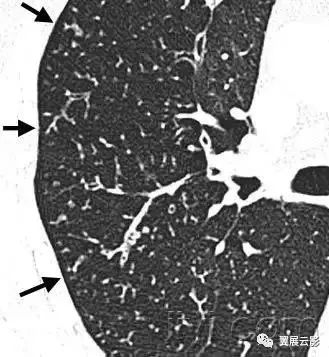

三十九、马赛克征

CT:本征象表现为不同的密度成片状镶嵌,可为间质性病变、闭塞性小气道病变(图)或者血管阻塞性疾病。马赛克征比马赛克样少血或者低灌注具有更强的诊断含义。由于支气管或细支气管阻塞导致的空气滞留可以导致局部的密度减低,在呼气相CT上表现更加明显。

该征象也可以见于间质性肺部疾病,特征是磨玻璃影,此时高密度代表间质性病变,低密度代表正常的肺。